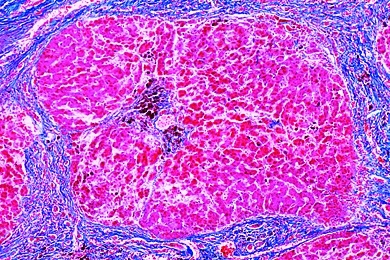

Mikropräparate in Serie - Pathologische Histologie des Menschen, Basisserie, 50 Präparate mit Begleittext

Pathologische Histologie des Menschen, Basisserie 50 Präparate mit ausführlichem Begleittext,

Inhalt:

- Krankhafte Veränderungen der Zellen und Gewebe - 9201e Parenchymatöse fettige Degeneration der Leber (Trübe Schwellung)

- 9202e Hämosiderosis der Leber. Berlinerblau-Reaktion - 9203e Glykoneogenie in der Niere (Glykogen-Niere)

- 9204e Pigmentzirrhose der Leber - 9205e Nekrotisierende Oesophagitis

- 9206e Fremdkörper-Granulom mit Hämosiderin und Riesenzellen - 9207e Mandelentzündung, Tonsillitis

- 9208t Leberzirrhose -- Schädigungen der Kreislauforgane (Herz, Gefäße) und der blutbildenden Organe - 9209e Fettherz, Adipositas cordis

- 9210e Herzschwielen - 9211e Chronische Herzmuskelentzündung, rezidivierend

- 9212e Organisierte Venenthrombose im Wadenmuskel - 9213e Milzinfarkt

- 9214e Chronische myelische Leukämie der Milz - 9215g Malaria-Melanämie der Milzb -- Pathologische Veränderungen der Lunge und der Leber;

Tuberkulose und Lungenentzündung

- 9216e Kohlenstaublunge, Anthracosis pulmonum - 9217e Hämorrhagischer Infarkt (Roter Keil) in der Lunge

- 9218e Grippepneumonie (Grippe-Lunge) - 9219e Kruppöse Pneumonie (Pneumonia crouposa)

- 9220e Chronische Pneumonie (Pneumonia chronica) - 9221e Nekrotische käsige Pneumonie

- 9222e Miliartuberkulose der Lunge - 9223e Chronische tuberkulöse Lungenkaverne mit Bakterien

- 9224e Stauungsikterus der Leber, Icterus hepatis -- Reaktionen der Nieren bei Arteriosklerose, Stoffwechselstörungen und Entzündungen; Dickdarmentzündung

- 9225e Schrumpfniere (Glomerularatrophie) - 9226e Amyloid-Degeneration der Niere (Amyloidose)

- 9227e Akute hämorrhagische Nierenentzündung (Nephritis) - 9228e Chronische Glomerulonephritis

- 9229e Embolische, nicht eitrige Glomerulonephritis

- 9230e Colitis bei Shiga-Kruse-Ruhr (Giftruhr) -- Spezifische Entzündungen bei Infektion mit Syphilis-Spirochaeten

- 9231g Konnatale Syphilis der Leber, Spirochaeten versilbert nach Levaditi * - 9232f Konnatale Syphilis der Leber (Feuersteinleber)

- 9233f Gumma testis, im Tertiärstadium der Syphilis - Fortschreitende Veränderungen geschädigter Gewebe und Organe (Hypertrophie und Hyperplasie)

- 9234e Balggeschwulst, Atheroma capitis

- 9235e Kropf, Struma colloides - 9236f Leistenhoden mit Hyperplasie der Leydigschen Zellen

- 9237e Prostatahypertrophie

- 9238f Riesenzellen-Granulom des Oberkiefers, Epulis giganto-cellularis -- Histologie der gut- und bösartigen Geschwülste

- 9239e Knorpelgeschwulst des Schambeins (Chondrom)

- 9240e Gebärmuttermyom (Myoma uteri) - 9241e Geschwulst der Brustdrüse, Fibroadenoma mammae

- 9242e Fibroepithelialer Mischtumor der Ohrspeicheldrüse - 9243e Melanosarkom der Haut

- 9244e Spindelzellensarkom - 9245e Karzinom am Hals der Gebärmutter, Carcinoma cervicis uteri - 9246e Hodengeschwulst, Sarcoma testis

- 9247e Papilläres Ovarialkystom - 9248e Gallertkrebs des Mastdarms, Carcinoma gelatinosum recti

- 9249e Lymphosarkom des Mittelfells, Lymphosarcoma mediastini - 9250e Lebermetastasen

Unsere Mikropräparate werden unter wissenschaftlicher Leitung hergestellt. Sachgemäß fixiertes und konserviertes Ausgangsmaterial ist die Voraussetzung für einwandfreie Präparate. Wir verwenden deshalb auf diese Arbeitsgänge besondere Sorgfalt. Die Herstellung der Mikrotomschnitte erfolgt durch erfahrene Fachkräfte, Schneidetechnik und Schnittdicke werden den Objekten angepaßt. Aus der großen Zahl der in der Mikroskopie üblichen Färbemethoden wählen wir solche, die eine klare und kontrastreiche Darstellung der gewünschten Strukturen mit bester Haltbarkeit verbinden. Meist handelt es sich dabei um Mehrfachfärbungen.